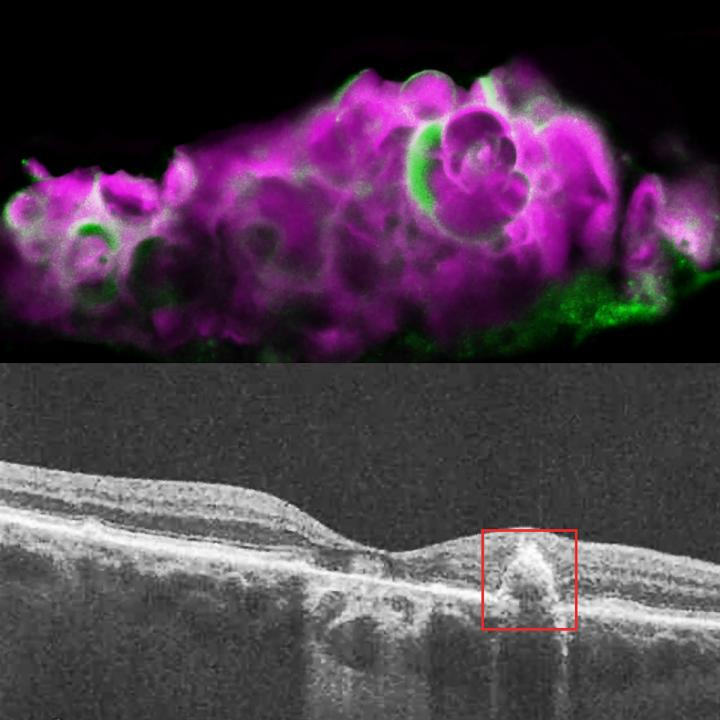

image: Top: HAP spherules (pink) and amelotin protein (green) in soft drusen from eye with dry AMD. Bottom: OCT image of eye with dry AMD, showing soft drusen beneath the retinal pigment epithelium.

Recently, researchers found a calcium-containing mineral compound called hydroxyapatite (HAP) in dry AMD deposits. HAP is a key component of tooth enamel and bone. Small balls of HAP filled with cholesterol, called spherules, were found only in drusen from people with dry AMD, and not in those with wet AMD or without AMD.

To verify that their cell culture model was accurately representing dry AMD, the researchers examined human cadaver eyes with dry AMD, wet AMD, or without AMD. They found HAP and amelotin only in the eyes with dry AMD, and not in the other eyes. While amelotin was found sometimes in areas of dry AMD without drusen, it was primarily present in soft drusen areas with large deposits of HAP.